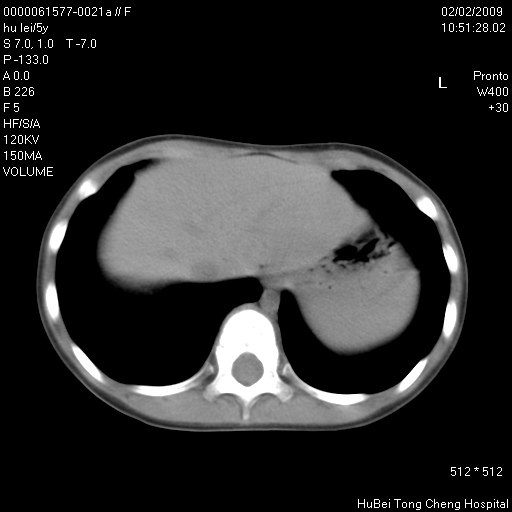

标题: PED1732:M5Y,右肺囊性占位!

患者:男,5。无明显不适,拍胸片考虑右肺囊肿。

行ct扫描,图象如下: